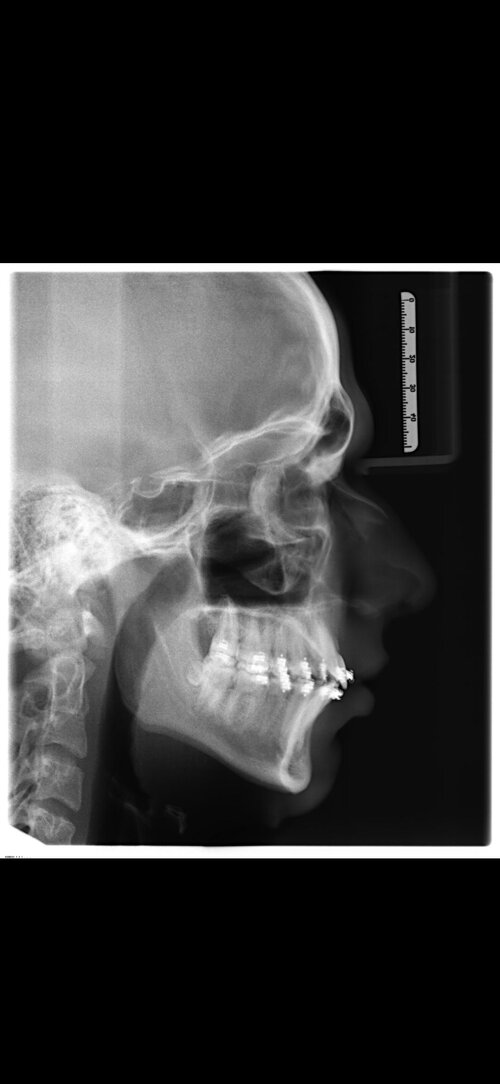

I'm getting bimax surgery in 8 days, performed by Dr Dr Kater (Frankfurt am Main, Germany). I'm 17 and i'm paying private, here's what i think rn:

3. I'm getting Bimax + tiny CCW rotation and a Genioplasty

5. It'll be a aesthetic/functional bimax